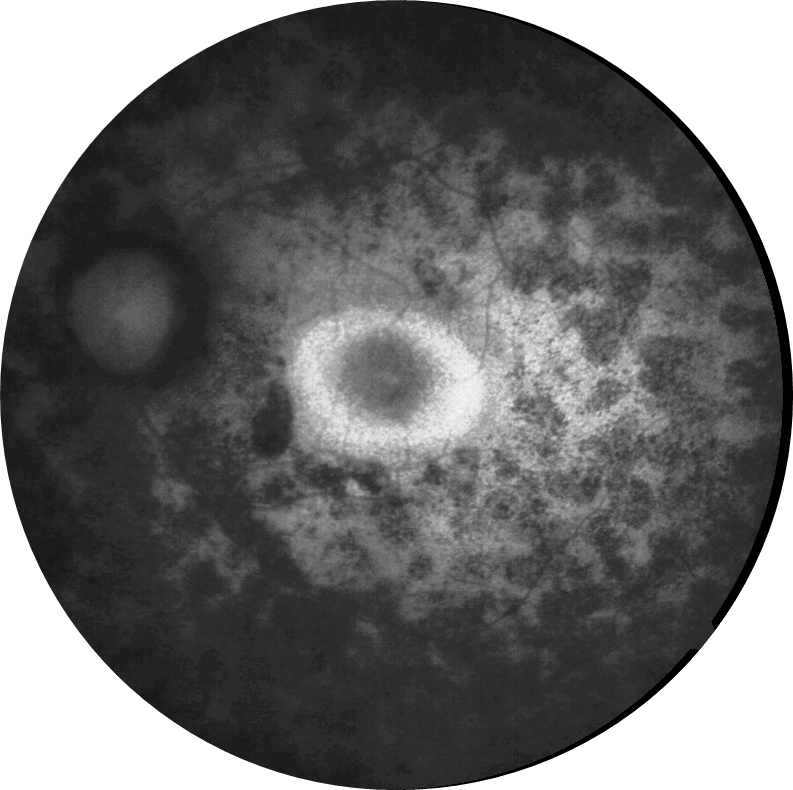

Kliniğimize her iki gözde çocuk yaştan bu yana gittikçe artan görme azlığı şikayetiyle 29 ve 21 yaşındaki iki kardeş başvurmuştur. 29 yaşındaki kardeşin her iki gözde görme keskinliği 3 mps düzeyinde iken 21 yaşındaki kardeşin 0,2 düzeyindedir. Hastaların her iki göz fundus otofloresans görüntülerini görmektesiniz. Bu bulgulara göre tanınız nedir? Lütfen cevabınızı aşağıya yazınız.

Bu ay size her iki gözde çocuk yaştan bu yana gittikçe artan görme azlığı şikayeti olan 29 ve 21 yaşındaki iki kardeşin fundus otofloresans görüntüleri eşliğinde tanılarını sormuştuk.

Tanı: Retinitis pigmentosa ’dır.

RP hastalarında, otofloresan görüntülemede zamanla daralan ve hastalık ilerlemesinin bir belirteci olarak hareket eden bir hiperotofloresan halka ortaya çıkabilmektedir. Bu halkanın dış sınırının içindeki fotoreseptöre atfedilen katmanların nispeten korunduğu, halkanın dış sınırının dışında ise elipsoid bölge ve dış limitan membran kaybı ile fotoreseptör katmanlarının incelmesi ve dış nükleer katmanın incelmesi veya yokluğu gözlemlenebilmektedir.